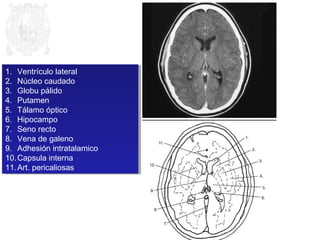

1. Ventrículo lateral

2. Núcleo caudado

3. Globu pálido

4. Putamen

5. Tálamo óptico

6. Hipocampo

7. Seno recto

8. Vena de galeno

9. Adhesión intratalamico

10.Capsula interna

11.Art. pericaliosas